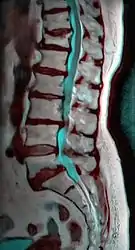

MRI of L5-S1 anterolisthesis

Anterolisthesis L5/S1

Anterolisthesis L5/S1. Blue arrow normal pars interarticularis. Red arrow is a break in pars interarticularis